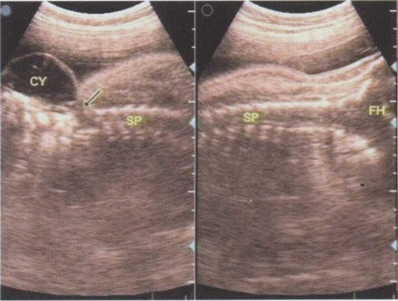

48.36周胎儿脊柱超声检查如图,根据声像图,初步诊断应该为()